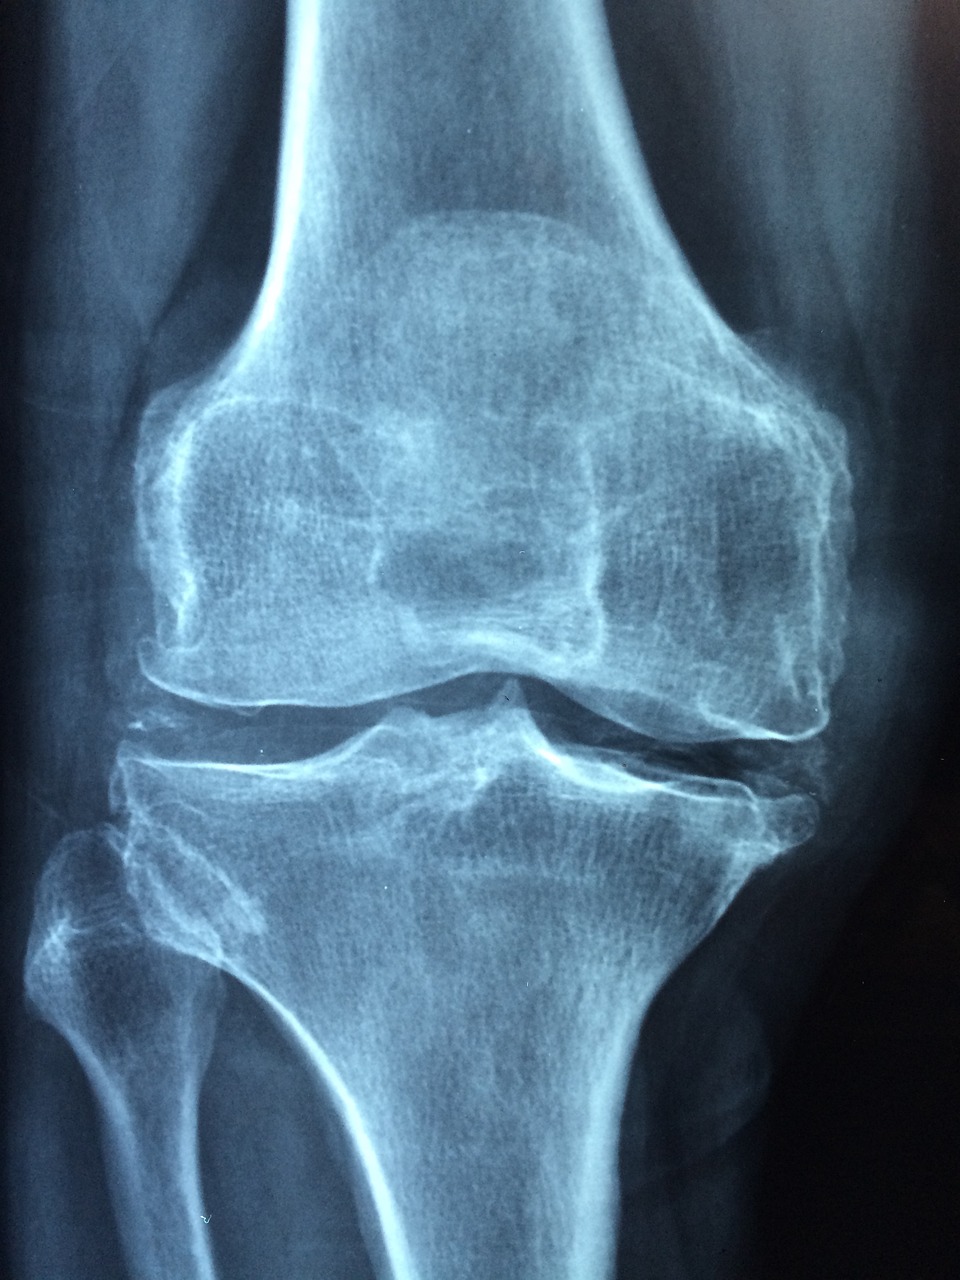

- 이러한 무릎에서의 소리는 대부분 무해하며, 건강에 직접적인 영향을 미치지 않습니다. 하지만 만약 무릎이 아프거나 부종이 동반된다면 전문의와 상담하는 것이 좋습니다. 무릎 관절 건강을 유지하기 위해 균형 잡힌 운동, 적절한 체중 유지, 관절을 힘들게 하는 활동을 피하는 것이 도움이 될 수 있습니다.